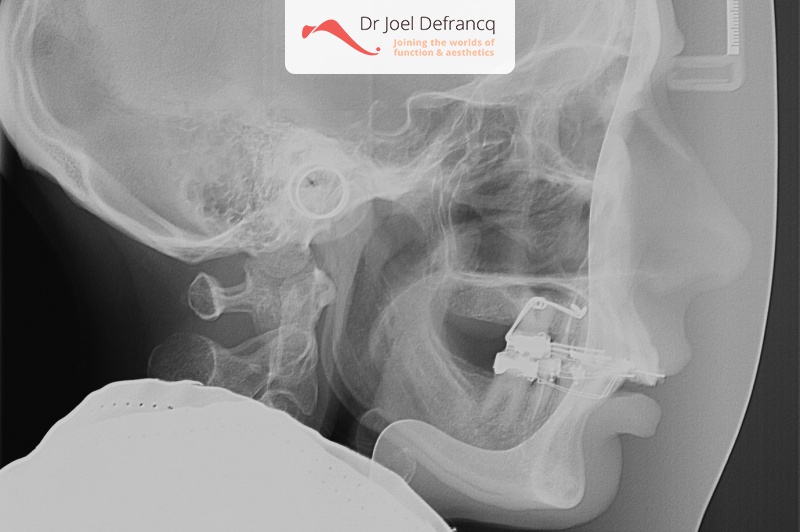

- Te kleine onderkaak (Overbeet)

- Diepe beet, vierkant gezicht

Kaakchirurgie

- Verlenging onderkaak (BSSO)

- Kinchirurgie

- Onderrand shaving der onderkaak